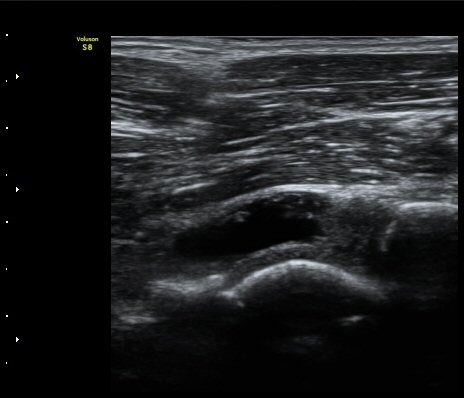

[ÆÈ²ÞÄ¡] ÆÈ²ÞÄ¡ °üÀý³» À¯¸®Ã¼¿¡ ÀÇÇÑ ÆÈ²ÞÄ¡ ÅðÇ༺ °üÀý¿°

³²ÀÚ/ 44¼¼

ÁÖÁõ»ó

ÆÈ±ÀÄ¡ ÅëÁõ

ÃÊÀ½ÆÄ °Ë»ç